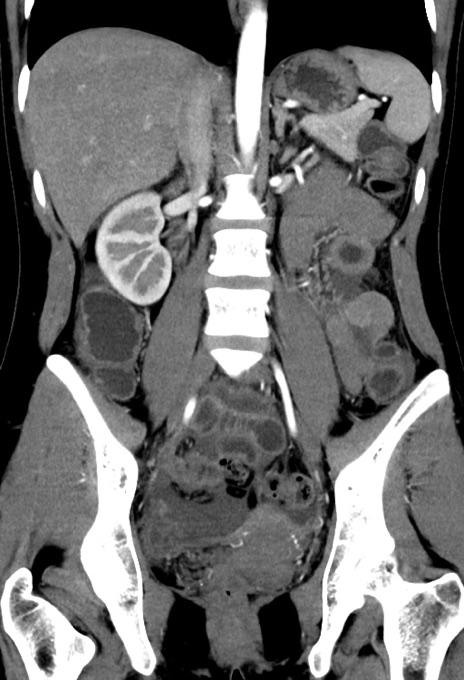

症例17(冠状断像)

【症例】20歳代女性

【主訴】嘔吐、下腹部痛

【現病歴】昨日夕食後に嘔吐し下腹部痛が出現。本日になっても嘔吐持続し改善しないため来院。

【身体所見】意識清明、BT 37.2℃、BP 108/67mmHg、腹部:平坦、やや硬、下腹部正中から右にかけて圧痛あり、反跳痛軽度あり、tapping pain(+)。

【データ】WBC 13600、CRP 14.94